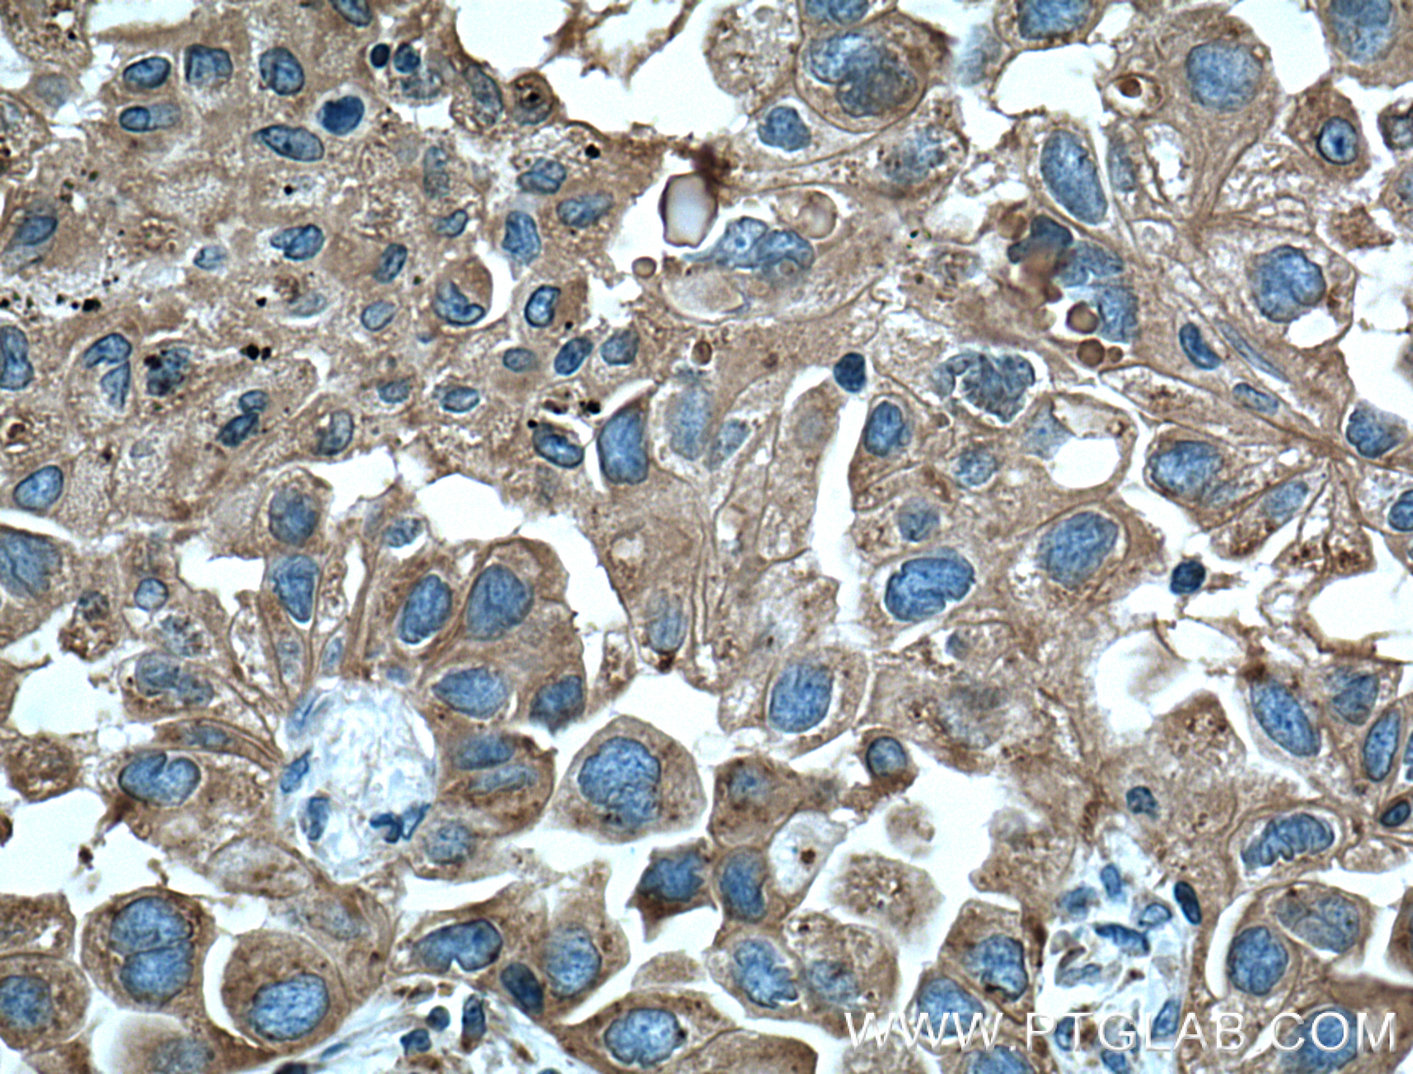

| Positive IHC detected in | human liver cancer tissue, mouse liver tissue, human lung cancer tissue, human liver tissue, human kidney tissue Note: suggested antigen retrieval with TE buffer pH 9.0; (*) Alternatively, antigen retrieval may be performed with citrate buffer pH 6.0 |

| Immunohistochemistry (IHC) | IHC : 1:500-1:2000 |